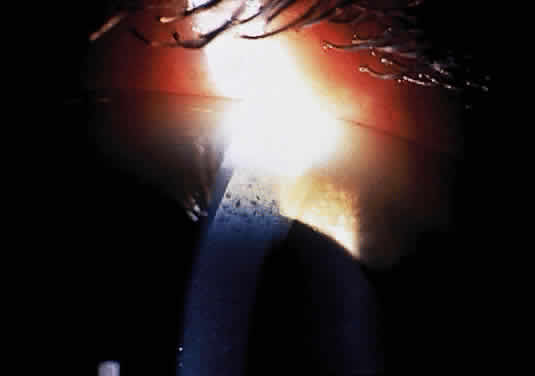

Corneal clouding (Fig. 10), hyperopic astigmatism, and a mild retinopathy with surface-wrinkling maculopathy (Fig. 11) appear to be the constant ocular triad.75 Some patients have retinal vascular tortuosity, optic nerve head swelling (Fig. 12), visual field defects, and abnormalities in color vision. Visual complaints are uncommon.

Fig. 10. Mild corneal clouding in a child with mucolipidosis III. (Traboulsi E, Maumenee I: Ophthalmologic findings in mucolipidosis III. Am J Ophthalmol 102:529, 1986)